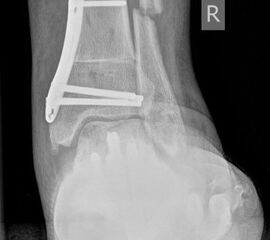

• Fuß belastet dp und seitlich (Abb. 14 und 15)

• Saltzman view (Abb. 16)

Zum Lesen der Bildbeschreibung und zur Vollansicht bitte die Bilder anklicken. Bilder: A. Simon

Typische Merkmale der Standard-dp-Röntgenaufnahme des Fußes im Stand

• Talus und Calcaneus verlaufen fast parallel

• Os naviculare ist gegenüber dem Talus nach medial gedrängt

• Metatarsalia überlappen sich basisnah

• Metatarsale I erscheint verkürzt

• Metatarsus adductus

Typische Merkmale der Standard-Seitaufnahme des Fußes im Stand

• Knöchelgabel ist außen rotiert

• Sinus tarsi ist einsehbar

• Subtalare Gelenklinie verläuft horizontal und ist breit einsehbar

• Der Abstand Malleolus medialis zum Os naviculare ist verkürzt

• Der Calcaneus erscheint verkürzt

• Der Krümmungsscheitel des Fußes ist erhöht

• Calcaneus pitch ist meist erhöht, der Rückfuß Equinus ist eher selten 12

Typische Merkmale des Saltzman View

• Calcaneus steht varisch zur Tibialängsachse

• Der erste Zehenstrahl ist medial erkennbar

• Konsekutive varische Gelenklinie des oberen Sprunggelenkes